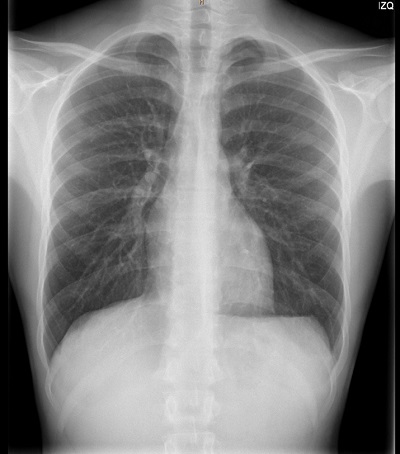

A las 6 semanas del primer episodio, presenta otro neumotórax izquierdo. Durante el segundo ingreso se realiza una tomografía computarizada (TC) de tórax donde se aprecian bullas apicales bilaterales (Fig. 2). Tras 6 días de ingreso, es dado de alta con mejoría clínica y radiológica. Finalmente es intervenido quirúrgicamente al mes del segundo episodio, sin presentar nuevas recidivas hasta la fecha actual.

| Figura 2. Imagen de TC de tórax sin contraste. Neumotórax izquierdo. Bullas subpleurales en ambas regiones apicales de los pulmones, sin signos de neumotórax derecho |